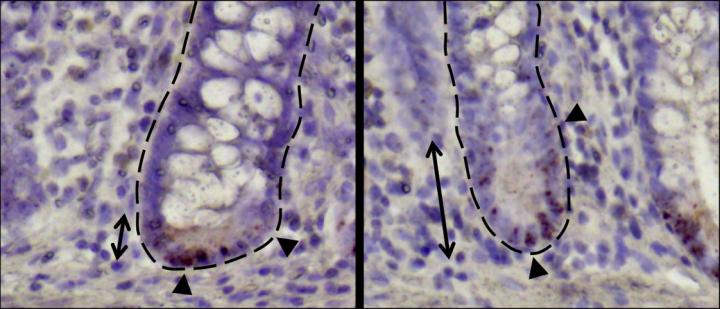

image: Small intestinal crypts of Crohn´s disease patients.

In addition to mouse studies, the researchers analyzed intestinal biopsies from Crohn's disease patients, characterizing the stem cell niche meticulously. After six months, the patients' intestines were examined again endoscopically focusing on finding signs of inflammation.

The study showed that microscopic alterations in stem cell niche were particularly prevalent in those patients who showed symptoms of a relapse of inflammation after six months.